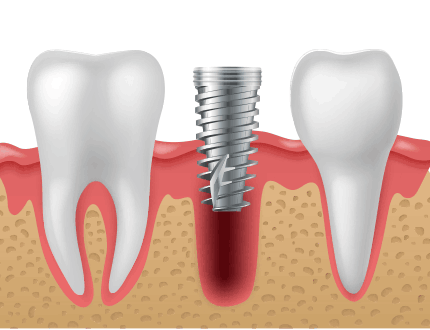

발치즉시 임플란트는 말그대로 보존이 불가능한 치아를 발치하자 마자 치아를 발치한 곳에 임플란트를 식립하는 술식을 말합니다.

발치 즉시 임플란트는 문제치아를 발치한 당일 바로 임플란트를 식립함으로써 여러 번의 시술, 마취에 대한 부담감이 적고

치료기간을 단축할 수 있는 고난이도 시술법입니다.

발치 후 즉시 임플란트를

식립하면 주변 잇몸 조직의

손상을 최소화할 수 있습니다.

잇몸과 잇몸뼈 상태가 양호하게 잘 보존되어 있는 경우에는 치아를 발치하고 곧바로 임플란트를 식립할 수 있습니다.

그렇기 때문에 이러한 발치즉시 임플란트는 수술횟수와 치료기간을 줄일 수 있을 뿐만 아니라

잇몸조직의 손상이 적어서 회복이 빠른 장점이 있습니다.

하지만 치조골이 부족하거나 잇몸에 염증이 심한 경우에는 발치후 즉시 임플란트가

어려울 수 있기 때문에 3차원 CT 촬영 등을 통한 정밀진단이 필요합니다.